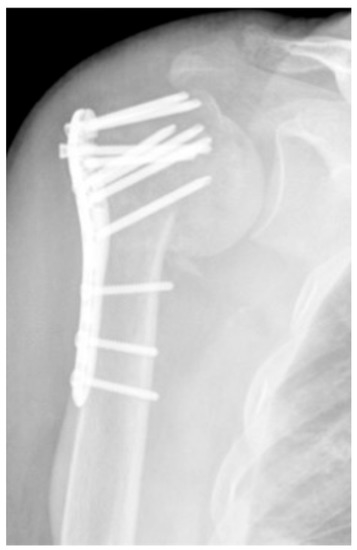

| Complication Type | Exemplary Images by X-rays or Pattern Images | Definition |

|---|---|---|

| 1 | ![]() | Complication Type 1 is defined by a mild, stable varus or valgus displacement (<20°) of the humeral head without resulting in a screw cutout through the humeral head cortex. |

| 2a | ![]() | Complication Type 2a is defined by varus displacement (<20°) of the humeral head associated with screw cutout through the humeral head cortex. The head sintering is considered relatively stable and non-progressive. |

| 2b | ![]() | Complication Type 2b is limited to displacement of the greater tuberosity, lesser tuberosity, or both tuberosities. |

| 2c | ![]() | Type 2c is defined by a severe varus displacement (>20°) of the humeral head, which is associated with a screw cutout at the humeral head in parallel to Type 2a. In contrast to Type 2a, this varus displacement is characterized by an unstable osteosynthesis situation and progression. |

| 3 | ![]() | Type 3 describes a displacement of the angular stable plate osteosynthesis with screw cutout/fracture avulsion in the humeral shaft region, while the humeral head position remains intact. |

| 4 | ![]() | Complication Type 4a is based on the presence of AVN of the humeral head without concomitant destruction of the glenoid articular surface due to an associated screw cutout through the humeral head cortex. |

| 4b | ![]() | Complication Type 4b is also based on the presence of an AVN of the humeral head combined with a destruction of the glenoid articular surface due to the associated screw cutout through the humeral head cortex. |